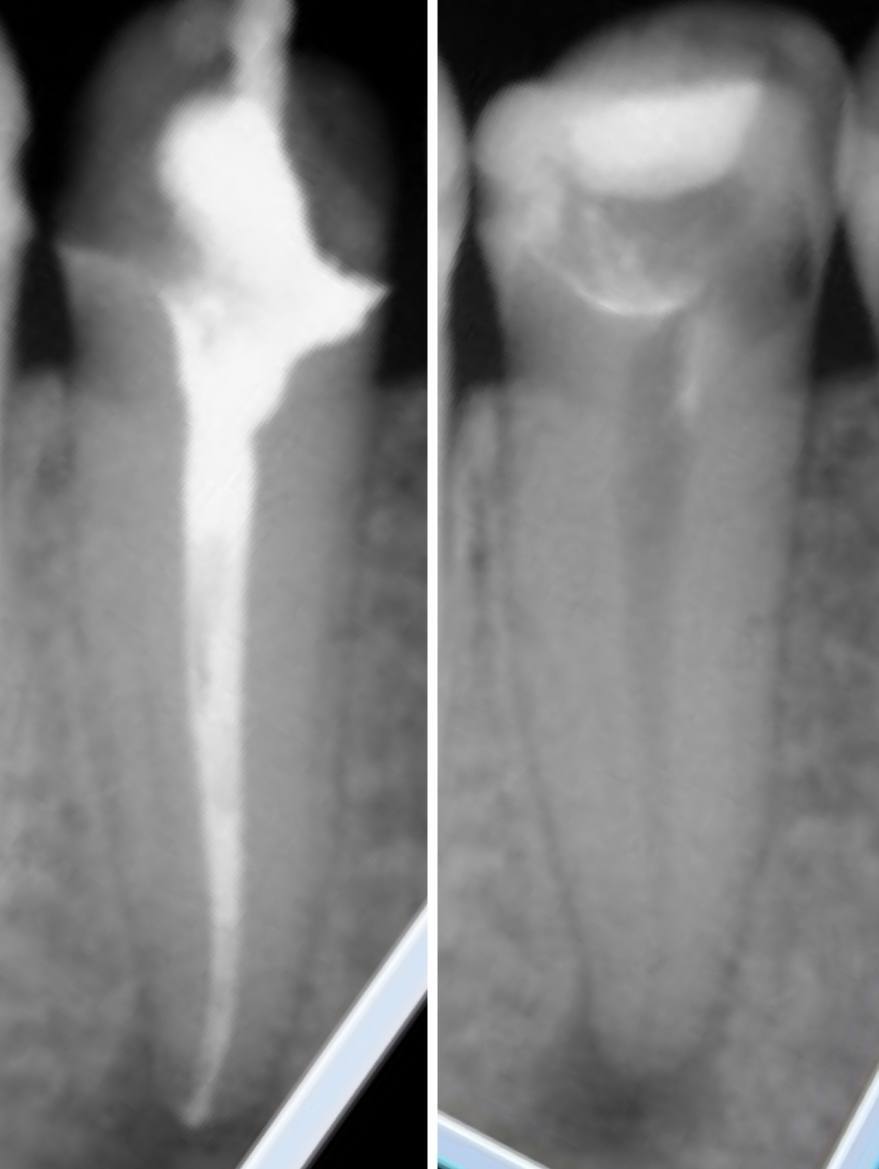

Поскольку часто причиной периодонтита является некачественное лечение корневых каналов, эндодонтическое лечение проводится с помощью дентального микроскопа и под рентгеновским контролем. Использование микроскопа и 3D-томографии позволяет врачу увидеть дополнительные каналы в зубе, определить их направление и длину, обнаружить и извлечь отломки инструментов.

Диспансерное наблюдение необходимо проводить для контроля динамики процесса.